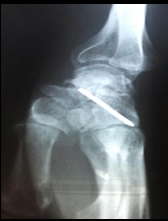

Bilateral Fenton's Syndrome: A Case Report and Literature Review